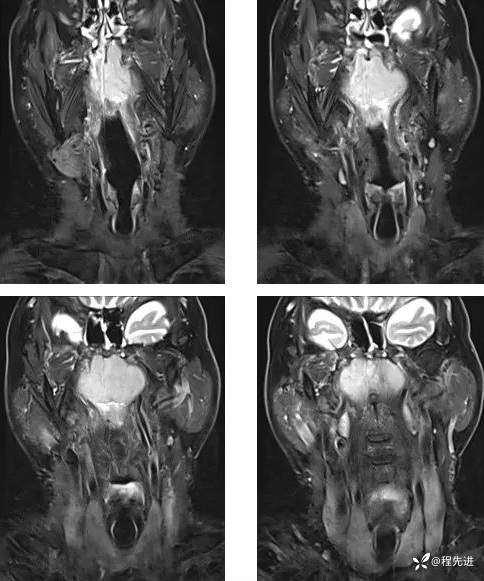

MR平扫+增强:

T1: